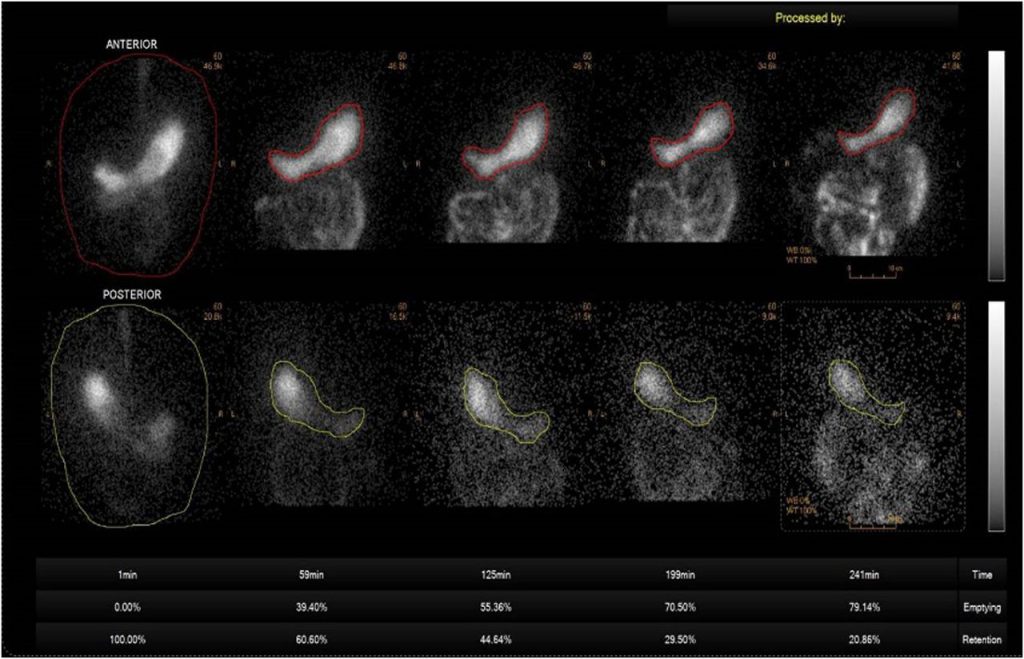

اسکن تخلیه معده یک روش تخصصی در پزشکی هستهای است که برای بررسی سرعت و نحوه تخلیه غذا از معده به روده انجام میشود. در این آزمایش، بیمار یک وعده غذایی سبک حاوی مقدار کمی ماده رادیواکتیو (رادیودارو) مصرف میکند و سپس با استفاده از دوربین گاما، تصاویر متوالی از معده ثبت میشود تا میزان باقیماندن غذا در زمانهای مشخص اندازهگیری شود. این روش دقیقترین تست برای تشخیص اختلالاتی مانند گاستروپارزی، تأخیر در تخلیه معده، تهوع و استفراغ مزمن، احساس پری زودرس و نفخ مداوم است.

برخلاف آندوسکوپی که بیشتر ساختار معده را بررسی میکند، اسکن تخلیه معده عملکرد واقعی و دینامیک معده را ارزیابی میکند. نتایج این تست معمولاً به صورت درصد باقیمانده غذا در معده طی دو تا چهار ساعت گزارش میشود و افزایش این درصد نشاندهنده کندی تخلیه است. میزان اشعه استفادهشده در این روش بسیار کم و ایمن است.

۴. تصویربرداری متوالی

تصویربرداری معمولاً به صورت متوالی و در فواصل زمانی مشخص (مثلاً هر ۱۵ تا ۳۰ دقیقه) انجام می شود تا حرکت ماده رادیواکتیو داخل معده در طول زمان ثبت شود. کل فرآیند تصویربرداری ممکن است بین ۱ تا ۳ ساعت طول بکشد تا پزشک بتواند روند تخلیه معده و عملکرد عضلات آن را به دقت بررسی کند.

تفسیر نتایج اسکن هسته ای معده نیازمند دقت و دانش تخصصی است تا بتوان به درستی وضعیت عملکرد معده را تشخیص داد. یکی از معیارهای مهم در این تفسیر، میزان تخلیه ماده رادیواکتیو از معده است. به طور معمول، اگر پس از گذشت ۲ ساعت از شروع اسکن، کمتر از ۴۰ درصد ماده رادیواکتیو از معده خارج شده باشد، این نشان دهنده تاخیر در تخلیه معده یا همان گاستروپارزیس است.